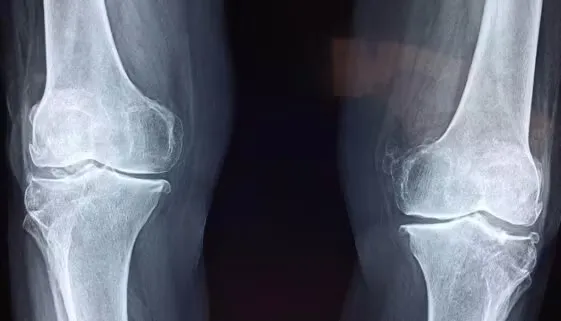

Rekonstrukcja łąkotki to zabieg chirurgiczny mający na celu przywrócenie funkcji stawu kolanowego po uszkodzeniu tej kluczowej struktury. Proces rekonwalescencji po takim zabiegu wymaga nie tylko […]